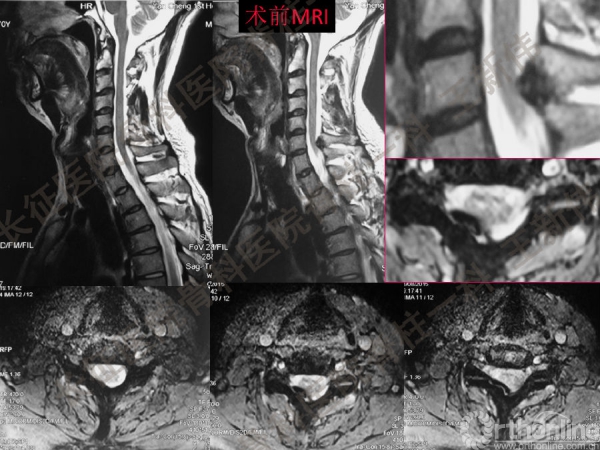

王新伟:颈椎后路通道下手术病例报告及文献回顾

颈椎后路通道下手术有哪些?颈椎后路通道下手术能做哪些事?颈椎后路通道下手术有哪些优势?长征医院骨科医院脊柱一科王新伟副教授通过临床病例报告及文献回顾,给出了他的答案——